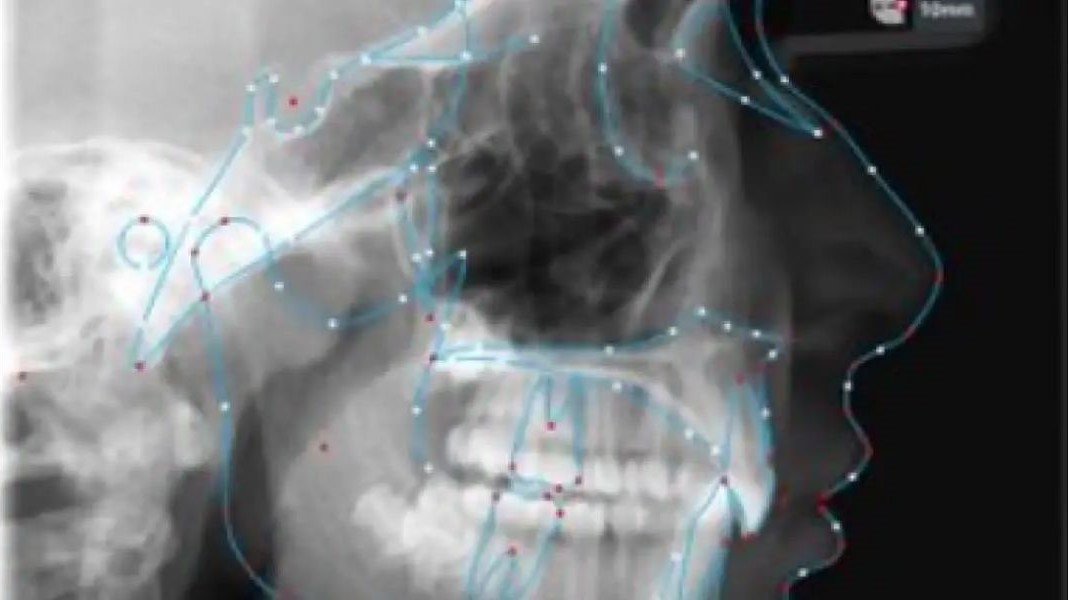

Tracing based on AI

With AI-powered tracing algorithms, we ensure that all dental landmarks are accurately and precisely traced on digital models. This feature allows for more accurate and efficient treatment planning and diagnosis, leading to better patient outcomes.